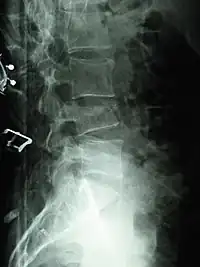

X-ray of the lumbar spine with a compression fracture of the third lumbar vertebra.

Compression fractures are usually diagnosed on spinal radiographs, where a wedge-shaped vertebra may be visible or there may be loss of height of the vertebra. In addition, bone density measurement may be performed to evaluate for osteoporosis. When a tumor is suspected as the underlying cause, or the fracture was caused by severe trauma, CT or MRI scans may be performed.